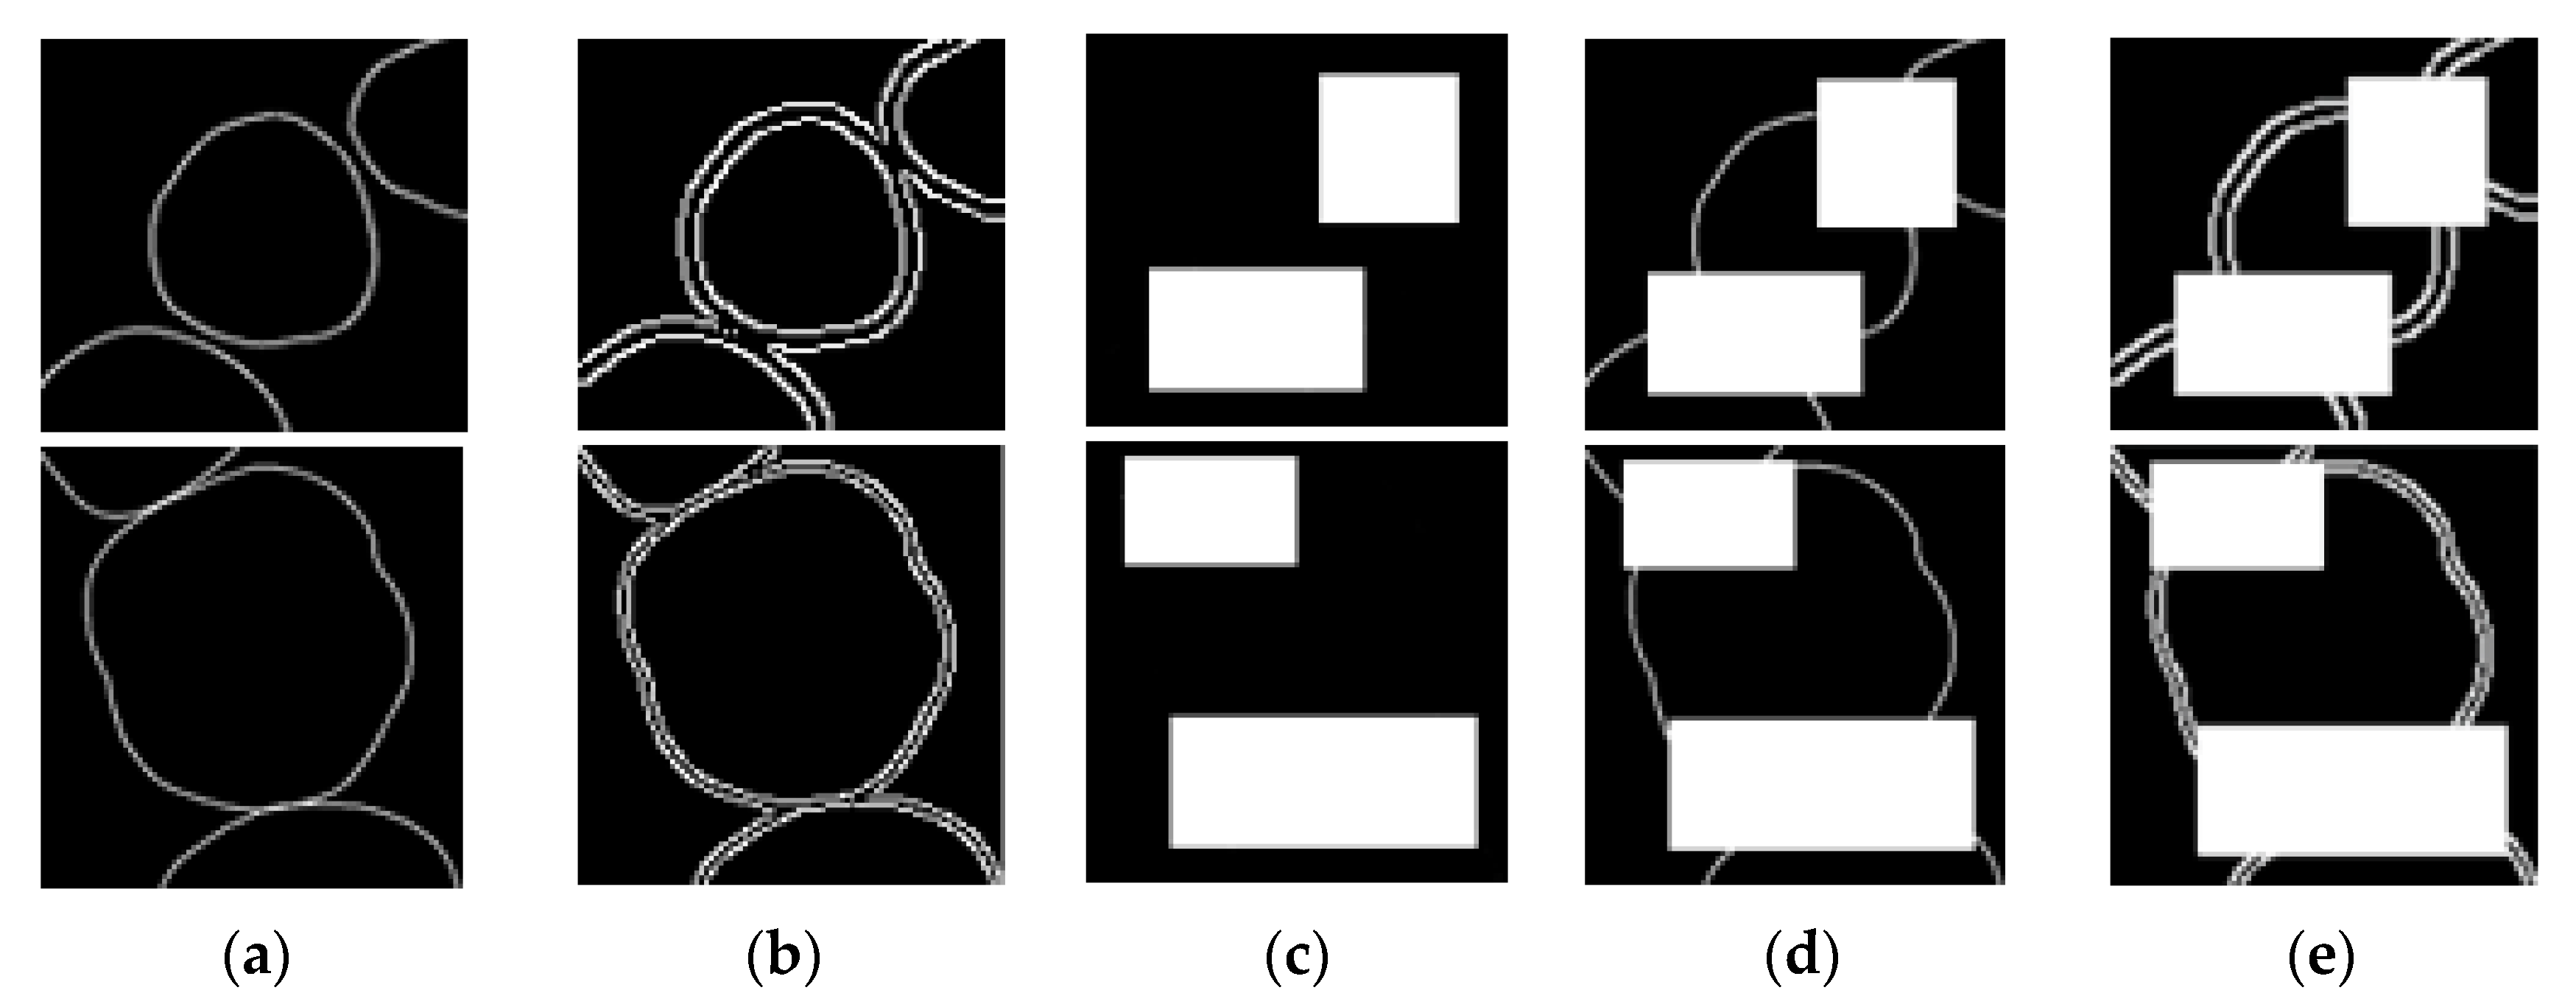

2.3. Training GAN

2.3.1. Data Preparation

2.3.2. Training Steps

3.1. Result of Image Completion